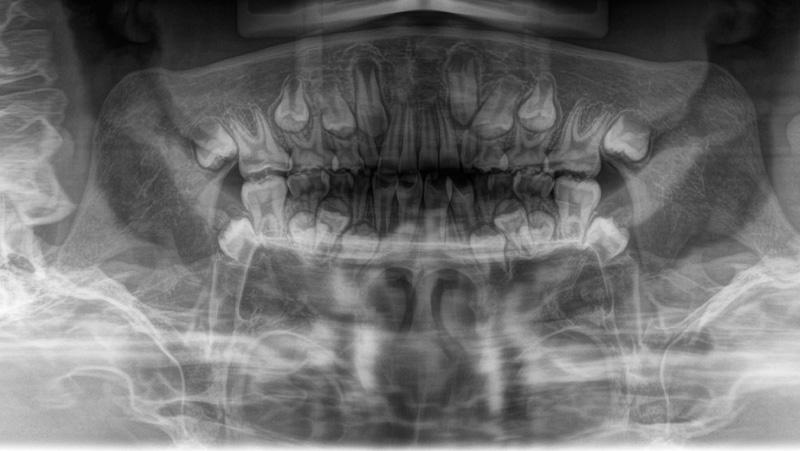

レントゲン図

| 診断 | ターミナルプレイン バーティカル 上下顎前歯叢生 |